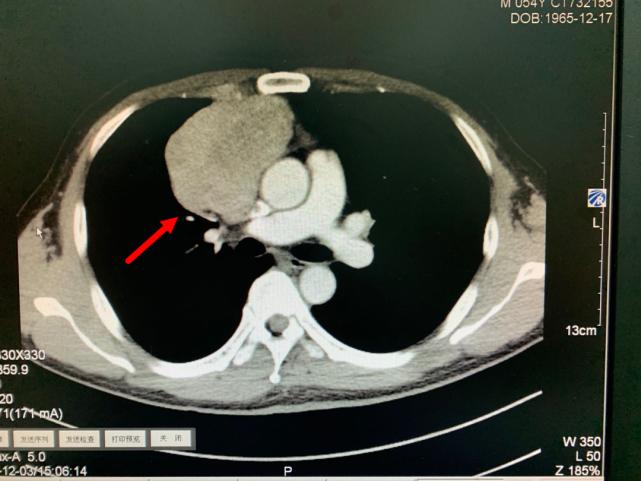

今年11月份,老方因“肠炎”在浙江省立同德医院肛肠科住院。“新冠”期间住院需要常规做胸部CT筛查,检查出来的结果却让他和医生们大吃一惊,胸部CT显示:胸腔内存在一个巨大肿瘤即纵膈肿瘤,大小约10.0cm×6.5cm×7.0cm,大小和一个成人男性拳头差不多。肿瘤紧靠着肺部、心室及大血管,且与部分大血管有粘连,对重要的脏器已经造成了挤压。在确定胃肠道没有严重病患后,老方被转入心胸外科进一步作检查、治疗。

箭头所指为巨大纵隔肿瘤

肿瘤与周围血管存在黏连

叶中瑞主任医师通过进一步增强CT检查发现,老方体内的肿瘤巨大、与相邻的重要脏器粘连,界限不清,手术难度较大,且微创手术不适合,于是采取正中劈开胸骨的手术方式。手术过程顺利,术后恢复良好。第二天即下床活动。术后病理结果显示:纵膈肿瘤性质为中度恶性的胸腺肿瘤,后续还需要做进一步的放射治疗,以防止复发。老方在庆辛之余,他告诉叶中瑞主任医师,自己从今年开始每年都按时做体检,争取做到疾病早发现、早治疗,避免错过疾病的最佳治疗时机。